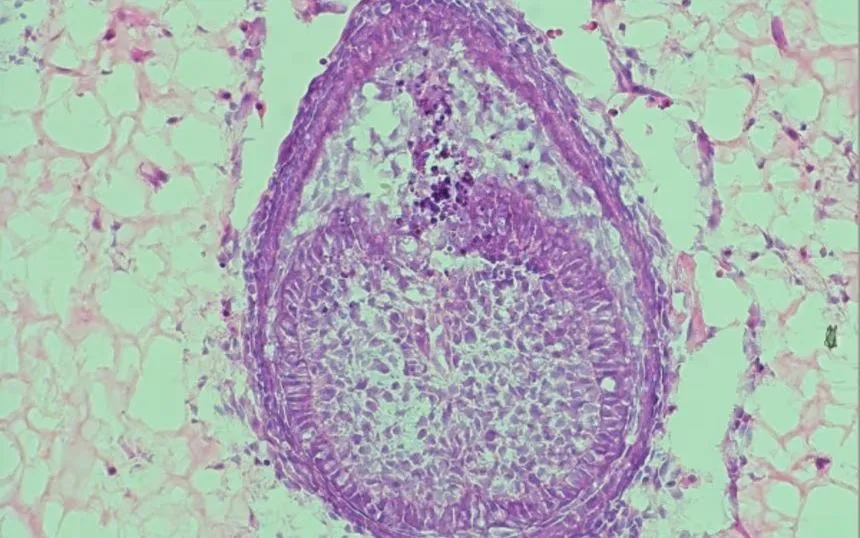

Mẫu lát cắt của cơ quan răng được nuôi trong phòng thí nghiệm tại King’s College London (Ảnh: Xuechen Zhang)

Theo bà Volponi, hai loại tế bào - gồm tế bào nướu người trưởng thành và tế bào mầm răng từ phôi chuột - tương tác với nhau trong quá trình tạo răng. Sau 8 ngày nuôi trong hydrogel, các cấu trúc giống răng đã hình thành.